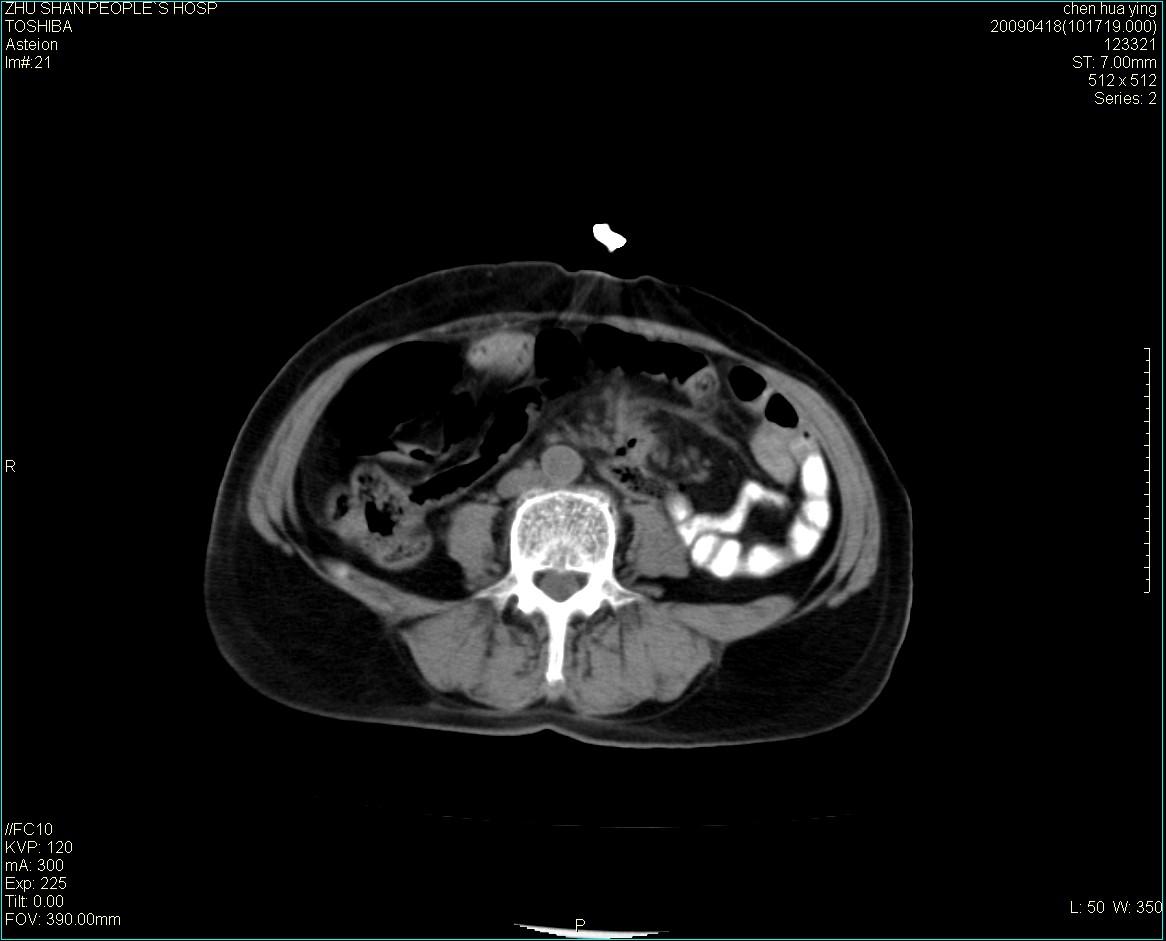

女性病人 65岁 腹部包块半年余结肠造影未见异常.

病灶略呈圆形有分叶状,上部层面呈实性,右侧见圆形低密度区,灶内见团块状钙化,病灶下方与肠管分境不清,考虑间质瘤可能性大,建议肠道准备后增强